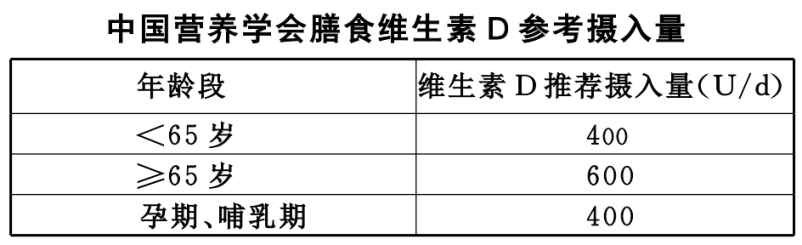

3、充足日照

维生素 D 除了来源于食物,还依靠阳光中的紫外线照射皮肤而合成。

充足日照,建议 11:00~15:00,暴露四肢及面部皮肤于阳光下 15~30 min(取决于日照时间、纬度、季节等因素),2 次/ 周,以促进体内维生素D的合成。

尽量不涂抹防晒霜,以免影响日照效果,但需注意避免强烈阳光照射,以免灼伤皮肤。

2、维生素 D(骨活化剂)

具有活性的维生素 D 能加强肠道内钙磷的吸收,调节 PTH 分泌及骨细胞的分化,促进骨形成;与钙剂合用时,剂量宜小,防止高钙血症的发生。

维生素 D 经肝、肾羟化后形成 1,25(OH)2D3 为最终活性物质,直接参与骨矿物质代谢。

老年人一般维生素 D 吸收代谢(羟化)功能下降,影响钙的吸收,应适当补充。老年人每日维生素 D 摄取量为 400~800 U。

罗钙全是具有活性的维生素 D(1,25(OH)2D3),无须经肝、肾羟化,直接参与骨矿代谢。每日口服 0.25~0.5ug。

阿法骨化醇只需经肝羟化为 1,25(OH)2D3,参与骨矿物质代谢,所以肾功能不全者亦可应用。0.5~1.0 ug/d,需长期服用(3~6 个月或更长)。

紫外线可促进维生素 D 的合成,增加骨矿含量,可以采用日光浴或人工紫外线照射。